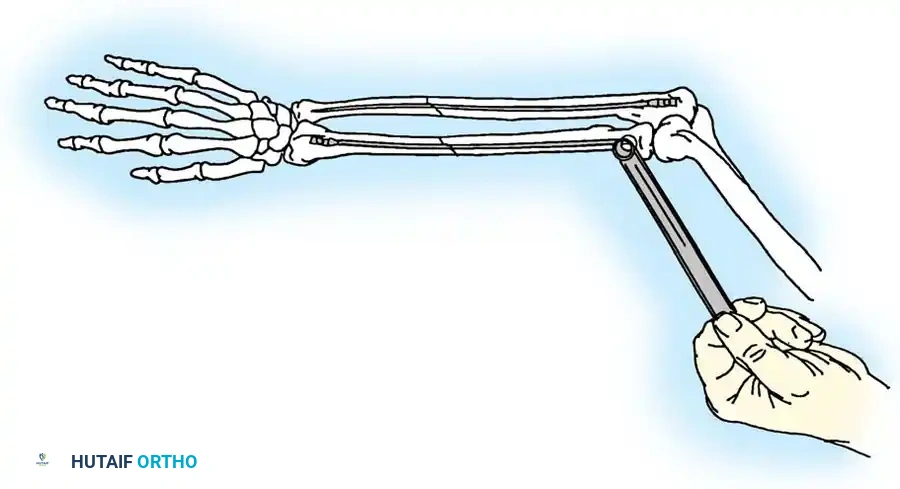

🔪 Surgical Technique: K-Wire and Tension Band (AO Technique)

- Reduction: Anatomically reduce the fragments and hold them temporarily with a reduction clamp.

- K-Wire Insertion: Introduce two parallel K-wires longitudinally from the tip of the olecranon across the fracture site. Direct them slightly anteriorly so they engage the anterior ulnar cortex distal to the coronoid process.

- Wire Loop: Pass an 18-gauge wire through a transverse drill hole in the distal fragment. Cross the wire in a figure-of-eight fashion over the posterior surface.

- Proximal Capture: Pass the wire around the protruding proximal ends of the K-wires.

- Double Twist: Weber and Vasey suggest twisting both limbs of the figure-of-eight loop. This double-twist modification ensures uniform compression across the fracture site.

- Securing K-wires: Bend the proximal ends of the K-wires 180 degrees, cut them short, and tap the bent ends deep into the triceps insertion and proximal bone to prevent symptomatic hardware prominence and migration.

Fig. 54-56 A and B, Transverse olecranon fracture repaired with Kirschner wires and tension band technique. C, Double twist modification of wiring suggested by Weber and Vasey.